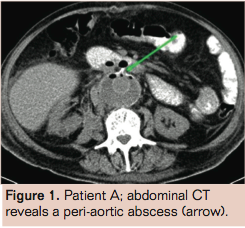

Patient A is a 78-year-old male with a history of Billroth 1 gastric resection, coronary artery bypass grafting, lung carcinoma (T1N0M0 treated with radiotherapy), a venous supragenual femoral-popliteal bypass, percutaneous transluminal angioplasty, chronic obstructive pulmonary disease GOLD 2, hypertension, and hypercholesterolemia. He presented with a ruptured aneurysm of the abdominal aorta with a diameter of 7.0 cm on computed tomography (CT) angiography with no signs of infection or inflammation. Emergency open aneurysm repair was performed with a Dacron prosthesis (DuPont). After surgery, he was admitted to the intensive care unit (ICU) for 2 days where he developed pneumonia (Escherichia coli), which was treated with ceftriaxone, a broad-spectrum cephalosporin. At return to the vascular surgical ward, fever persisted. Common postoperative causes of infection were ruled out. CT angiography showed intraperitoneal and

retroperitoneal abscesses (Figure 1). CT-guided puncture of only the periprosthetic hematoma was performed. The other abscesses were not punctured and drained. Culture revealed a Listeria monocytogenes. Although L monocytogenes infection is commonly seen in patients with close contact to milk and cheese products, our patient had no history of eating or working with these products. The graft infection was discovered 2 weeks after initial operation, and was considered an unfavorable period for a relaparotomy. We believed graft removal was not feasible in this patient because of his poor nutritional status, recent pneumonia and recent postoperative status. Therefore we started conservative treatment. Antibiotics were switched to amoxicillin and gentamicin, according to sensitivity of the cultured micro-organism and administered intravenously during 6 subsequent weeks. Control abdominal CT showed a reduction